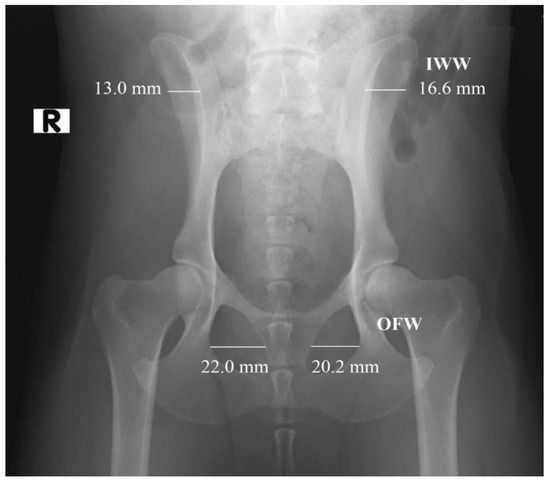

2.2. Radiographic Measurements

In the first part of the study, 203 radiographs in DICOM format were manually annotated using the polygonal image annotation tool, LabelMe [20], to delineate the right and left obturator foramina. The AIWW was calculated by measuring the widths of the right and left iliac wings in millimeters. A horizontal line was drawn between the dorsal and ventral iliac cortices at the cranial aspect of the sacroiliac joint on both sides (Figure 1). The AIWW was determined by subtracting the width of the right wing from that of the left [10]. The AOFW was calculated by measuring the widths of the right and left obturator foramina in millimeters. A horizontal line was drawn between the medial and lateral aspects of each foramen at its widest points (Figure 1). The AOFW was determined by subtracting the width of the right obturator foramen from that of the left [10]. The AIWW and AOFW, measured in millimeters (x), were used separately to estimate the degrees of pelvic rotation (y) through the following regression equations: y = 0.997x + 0.061 for AIWW and y = 1.644x − 0.912 for AOFW [10]. The AOFA was calculated by measuring the areas of the right and left obturator foramina in square millimeters. For this purpose, the areas were outlined using semantic segmentation, employing pixel-wise labeling to trace the boundaries of both obturator foramina (Figure 2). The AOFA was determined by subtracting the area of the right obturator foramen from that of the left.

Figure 1. Measurement of the widths of the right and left iliac wings (IWW) in millimeters (mm): horizontal lines were drawn between the dorsal and ventral iliac cortices at the cranial aspect of the sacroiliac joint on both sides. Measurement of the widths of the right and left obturator foramina (OFW) in mm: horizontal lines were drawn between the medial and lateral aspects of each foramen at their widest points. Asymmetry was calculated as the difference between the two measurements (largest minus smallest). R indicates the right side.